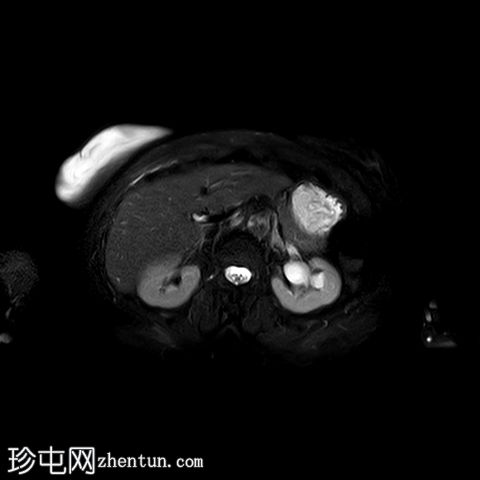

轴位

DWI

5.jpg

肿块最大轴向及头尾径约为 9.7 x 9.6 x 9.5 cm,T1 加权像呈低信号,T2 加权像呈中/高信号,伴有扩散受限和不均匀增强。

肿块前方压迫膀胱,后方紧邻乙状结肠,未见侵犯。

肿块压迫左侧远端输尿管,导致轻度输尿管肾积水。

MRI有助于确定病因,尤其是在非产褥期病例中(例如,子宫肌瘤、子宫肌肉瘤或子宫内膜恶性肿瘤),如本例所示。